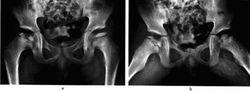

雙側股骨頭骨骺缺血性壞死(進展期)圖9-4雙側股骨頭骨骺缺血性壞死(進展期)

a.b 平片,示雙側股骨頭骨骺變扁.密度增商.其中右側頭骺及左側乾骺端夾雜囊變透亮區

左股骨頭骨骺缺血性壞死(進展期)圖9-6左股骨頭骨骺缺血性壞死(進展期)

。雙髖正位平片,左股骨頭骨骺變扁,密度均勻增高,骨紋消失,骺線不規則增寬,乾骺部稍增粗變短;b.MRI冠狀位T1Wl;c T2Wl;d T2Wl抑脂像,示左股骨頭骺變扁,並呈長T1短T2信號改變,乾骺端內側近骺板處見不規則長T1、長T2 異常信號,抑脂像顯示乾骺端水腫,關節囊少量積液